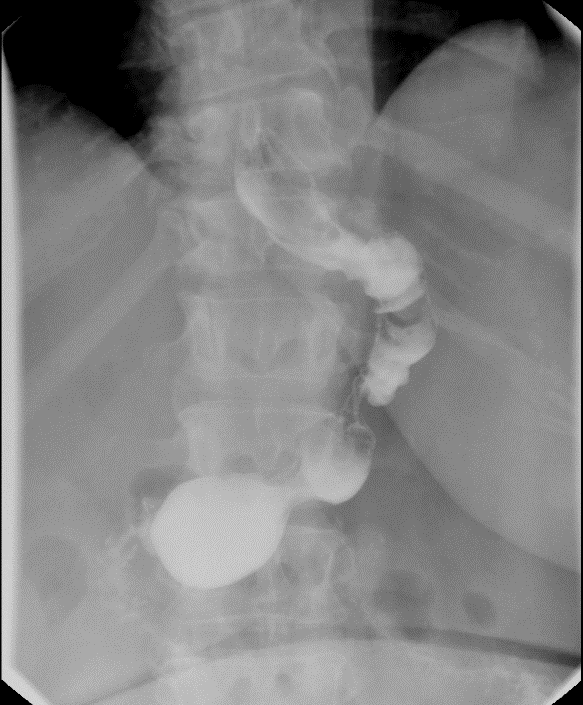

Defecography

Return to Table of Contents

- Indications:

- Method:

- Confirm that the patient had an adequate bowel prep.

- The technologist will have the patient drink approximately 300mL of thin barium.

- This barium will fill the small bowel so that it will be visible during the exam.

- Begin the exam approximately 20 - 30 minutes after the administration of the thin barium.

- During this time (if able), conduct a private interview with the patient, discussing the details of the anorectal problem and the purpose of the exam. The exam can be embarrassing and overwhelming for the patient and this can help put the patient at ease.

- When adequate time has passed from the barium ingestion, have the patient sit on the defecography chair as they would normally sit on the toilet.

- With the patient seated on the defecography chair, obtain a scout image of the rectum and pelvis.

(key image 1). Be sure to include:

- the sacrum posteriorly

- the pubic symphysis anteriorly

- approximately 5cm below the skin surface of the perineum

- This extra room inferiorly will able you to view any prolapse that may occur without having to move the fluoro machine.

- the centimeter marker on the commode

- the barium-filled small bowel superiorly

- After obtaining the scout image, lock the fluoro tower in place.

- Do not move the tower after you have taken the scout image.

- This will ensure that you are able to measure descent of the pelvic floor appropriately.

- Have the patient lie on the stretcher in the sims position.

- Perform a digital rectal exam.

- Evaluate for any masses or residual stool within the rectum.

- Evaluate anal sphincter tone.

- Evaluate for a rectocele.

- Lubricate the enema tip and place it into the patient’s rectum.

- With the help of the technologist, instill as much of the barium paste into the rectum as the patient will allow.

- The technologist will fill five (5) syringes with barium paste.

- While it is ideal to instill all of the contrast material, avoid producing a feeling of urgency for the patient.

- Remove the enema tip.

- Using your finger, place a small amount of barium paste on the skin around the external anal opening to mark its location.

- Have the patient sit up.

- When the patient is able, have them sit on the defecography chair.

- The patient can often become dizzy when sitting back up, so ensure that they are feeling well enough to stand.

- Obtain spot films while that patient performs the following maneuvers:

- Rest

(key image 2).

- Squeeze

(key image 3).

- This should be done with maximum voluntary contraction of the sphincter and pelvic floor muscles.

- Ask the patient to try and use their muscles as if they were trying to hold in a bowel movement.

- Strain

- Ask the patient to "bear down" or increase their abdominal pressure while trying not to have a bowel movement.

- Once you have obtained images during the “rest,” "squeeze," and "strain" maneuvers, have the patient evacuate the barium.

- Obtain a cine loop of the evacuation